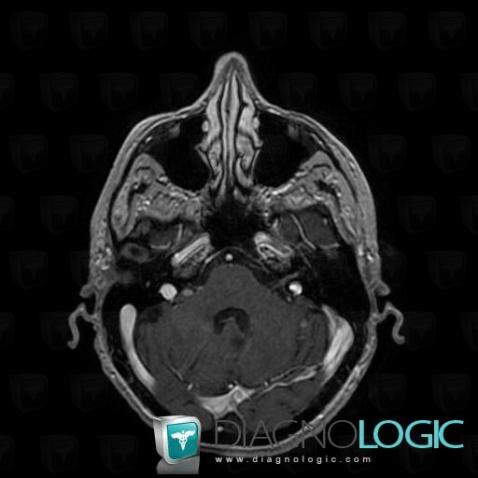

Les images ci-dessous illustrent ce dossier pour les diagnostics Carcinose méningée, Méningite carcinomateuse, pour les modalités (IRM)

Voici les informations spécifiques à l'image clé ci dessus:

- Diagnostic Méningite carcinomateuse, Localisation(s) Espaces peri cérébraux infratentoriels, comportant les gammes Anomalie des citernes de la base

Voici les informations spécifiques à l'image clé ci dessus:

- Diagnostic Carcinose méningée, Localisation(s) Nerfs VII VIII, comportant les gammes Lésion des nerfs VII / VIII